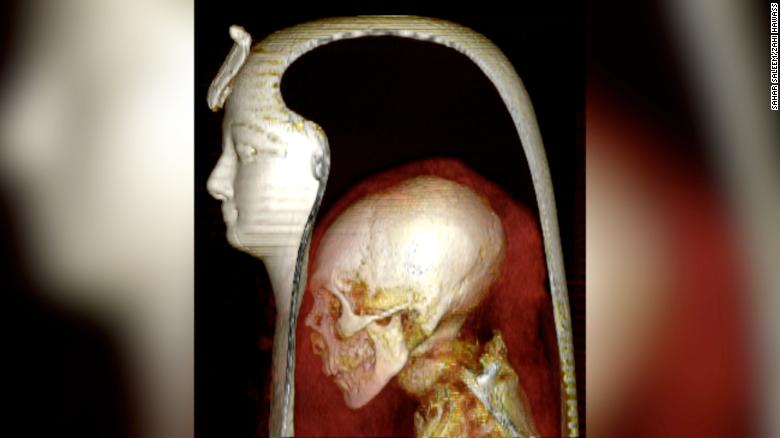

▼法老王「阿蒙霍特普一世」的木乃伊是1881年時在埃及南部發現的,他是唯一沒有被考古學家解開繃帶的木乃伊。最近考古學家首次用電腦斷層掃描等先進技術,在不碰觸遺體的情況下進行數位開箱,揭開他的神秘面紗。

▼本次研究是由開羅大學放射線學教授Sahar Saleem和知名埃及考古學家Zahi Hawass領導的。分析報告顯示,「阿蒙霍特普一世」是在35歲時過世的,他身高169公分,下巴比較窄、鼻子小、牙齒狀況良好,頭髮捲曲,而且健康狀況不錯。

▼目前「阿蒙霍特普一世」的離世原因還有待調查,考古學家表示他生前沒有罹患任何疾病的跡象,很可能是因為心臟病離世的。他是首位以雙臂交叉姿勢被製作成木乃伊,也是最後一個大腦未從顱骨中取出的法老。

考古學家還發現,「阿蒙霍特普一世」的陪葬珠寶非常豐富,其中包括30個護身符、一條鑲滿金珠的腰帶,這些都很有研究價值。